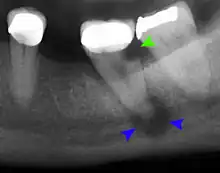

Mouth infections are usually diagnosed on history and physical exam in the dental office or at a clinic visit with an otolaryngologist.[2] Swelling within the oral cavity or cheeks, along with a history of progressively worsening tooth pain and fevers, is usually enough evidence to support the diagnosis of a mouth infection. Depending on the severity of the infection, further tests may include x-rays and CT scans of the mouth to better characterize the location and extent of the infection.[12] If the infection is drained with a needle or scalpel, then a swab of the infection is collected to identify the microbes present in the abscess and to determine their respective susceptibilities to antibiotics. Other lab tests may include a complete blood count with differential, serum electrolyte concentrations, and other routine assays for an infectious workup.[2][3]